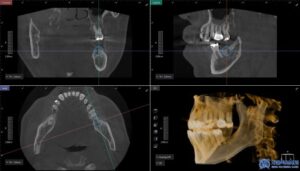

환자분은 좌측 아래쪽 어금니가 없는 상태였고,

오랫동안 방치되어 치조골(잇몸뼈)의

변화가 일부 있었습니다.

하지만 다행히도 임플란트를 식립하기에

충분한 골량이 유지되고 있었고,

무절개 방식으로 빠르게

임플란트를 진행할 수 있었습니다.

무절개 방식은 컴퓨터 분석을 통해

미리 임플란트의 식립 위치를 시뮬레이션하여,

수술 시 오차를 줄여주는 방법입니다.

수술 가이드를 활용하여 정확한 위치에

임플란트를 심기 때문에,

잇몸을 절개할 필요 없이 간편하고

안정적인 수술이 가능합니다.